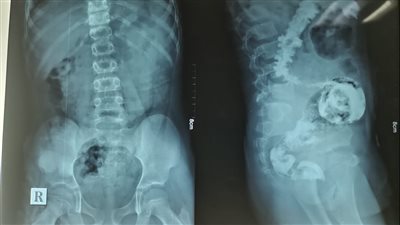

اجرت بنها النموذجي اول عملية قلب مفتوح بالمستشفي لاول مرة